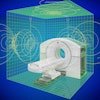

Absolute dose difference of 4D dose distributions considering ground truth motion versus reconstructed motion from either the PCA model (top) or the 2D translation model (bottom) prediction for three fields (the arrows indicate the field direction). All images courtesy of Ye Zhang.

Absolute dose difference of 4D dose distributions considering ground truth motion versus reconstructed motion from either the PCA model (top) or the 2D translation model (bottom) prediction for three fields (the arrows indicate the field direction). All images courtesy of Ye Zhang.At the PSI, the newest proton therapy gantry (Gantry2) is equipped with a beam's eye view (BEV) imaging system that can acquire 2D x-ray fluoroscopy images during proton therapy. But what's really needed is information regarding the 3D deformable motion throughout the whole target region. To achieve this, the PSI team has proposed a method for extracting 3D motion from surrogate motion detected using the BEV system (Physics in Medicine and Biology, 2013 November 21, Vol. 58:24, pp. 8621-8645).

To further investigate the feasibility of motion tracking for scanned proton beam therapy, the PSI team examined the effect of motion prediction errors on the resulting 4D dose distributions. For all subjects, they calculated 4D dose distributions (for a single field and using Gantry2's scanning parameters) using both the ground-truth motion and predicted motion. Predictions were performed using both the PCA model, where full 3D motion is reconstructed, and a translation model, in which every point in the liver is assigned the same motion vector of the fiducials.

Comparing absolute dose differences between ground truth-based and prediction-based plans (using fiducial markers) showed that motion predictions from the translation-only scenario were poor, with maximum dose differences of more than 50%. Plans based on PCA-predicted motion, on the other hand, were similar to those based on ground-truth motion. Here, absolute dose differences of more than 5% occurred in only 3.61% (median) or 15.13% (maximum) of dose calculation points in the irradiated volume. Similar results were seen when tracking diaphragm motion.